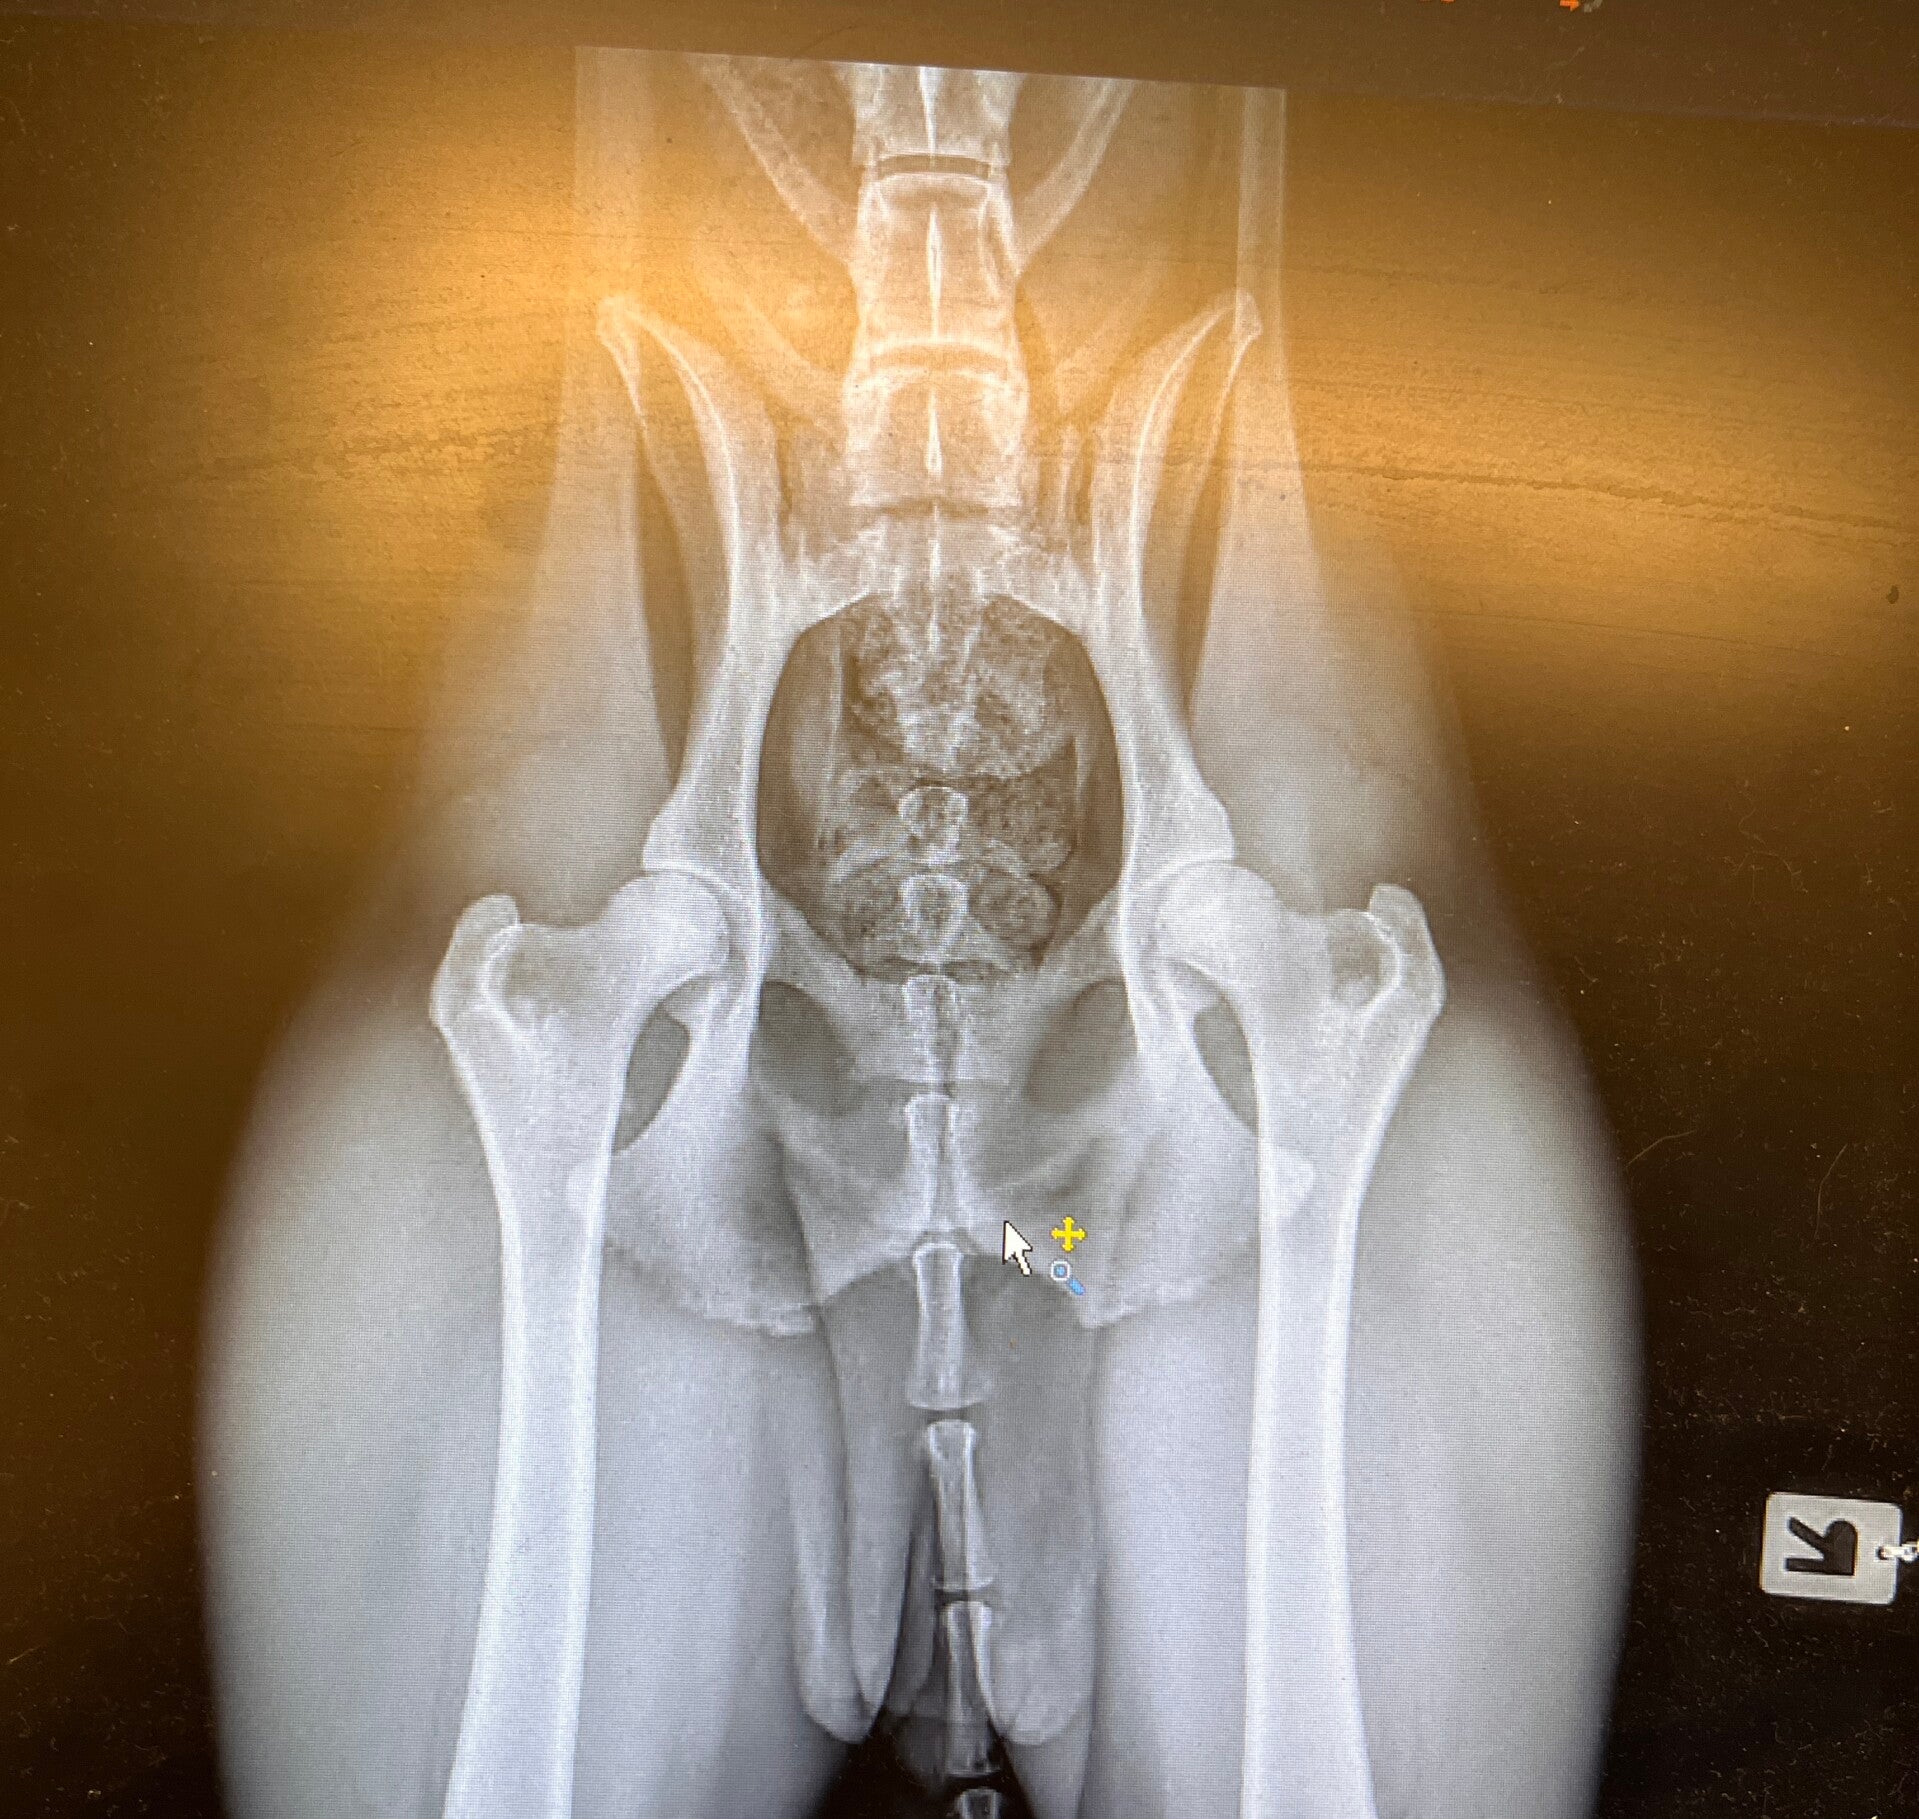

Eona wurde von Dr. Hofmann HD geröngt... Seine Prognose hat sich bestätigt.. Am 24.03.26 kam die offizielle Auswertung von Frau Dr. Viefhuss!

Wir freuen uns über HD-A1 ;o) Damit wäre dann die 2. Hürde geschafft!